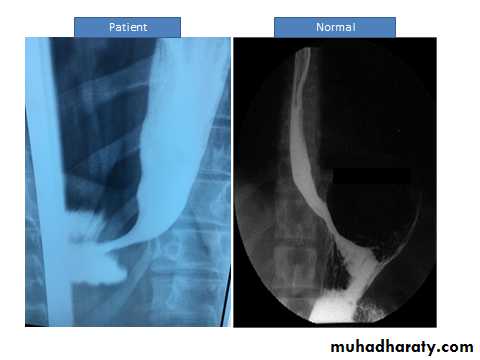

• A barium swallow shows tapered narrowing of the lower oesophagus. In late disease the oesophageal body is dilated, aperistaltic and food-filled.

Barium study (Barium swallowing)Birds Beak appearance in achalasia